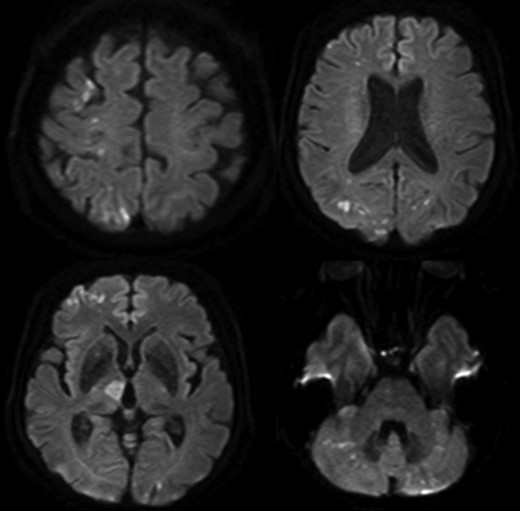

A 65-year-old woman admitted to a territorial hospital due to dizziness and listless feeling in the left arm. Magnetic resonance imaging revealed multiple CIs in the right frontal area and cerebellum on both sides (Fig. 1). Computed tomography angiography (CTA) detected stenosis in the IA and LSA (Fig. 2). No atrial fibrillation was detected despite repeated Holter-Electrocardiography. The patient was initially treated with aspirin, but thereafter experienced recurrent CIs. Clopidogrel was therefore added. Under double anti-platelet therapy, she suffered further CIs, and warfarin was added. However, CI occurred yet again. After six CIs, she was referred to our hospital.

Multiple cerebral infarctions in the right frontal area and cerebellum.